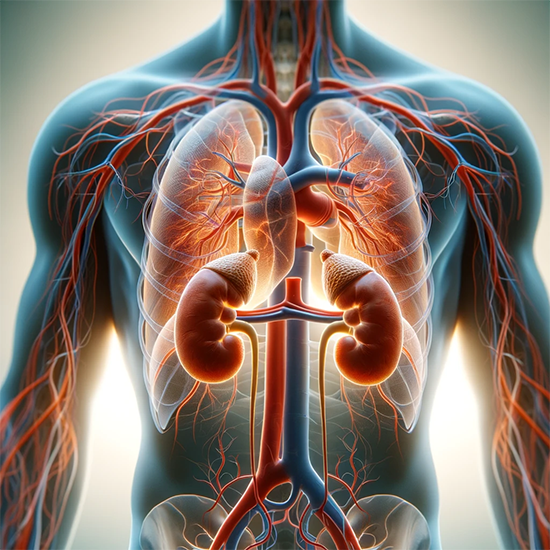

Adrenal insufficiency occurs when the adrenal gland fails to provide adequate levels of the stress hormone cortisol. This may occur through failure of the adrenal gland itself (primary adrenal failure commonly called Addison’s disease) or failure of the pituitary gland to stimulate normal cortisol levels from the adrenal gland (secondary adrenal insufficiency).

Primary adrenal insufficiency or Addison’s disease occurs in approximately 1 in 10 to 15,000 people and is more commonly found in women as autoimmunity is more common in women. Secondary adrenal insufficiency due to pituitary failure is twice as common as Addison’s disease and can affect both sexes equally.1

Adrenal insufficiency can be classified into primary, secondary, and tertiary causes. Primary adrenal insufficiency occurs when there is a pathology affecting the adrenal gland itself. Secondary adrenal insufficiency results from a decreased level of adrenocorticotropic hormone (ACTH) released from the pituitary gland, and tertiary adrenal insufficiency results from a decreased level of corticotrophin-releasing hormone (CRH) released from the hypothalamus.